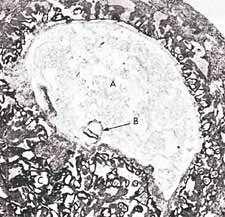

Figure 3: In this photomicrograph, we can see the suspension of an embryo (marked B) during the alaqah stage (about 15 days old) in the womb of the mother.  The actual size of the embryo is about 0.6 mm. (The Developing Human, Moore, 3rd ed., p. 66, from Histology, Leeson and Leeson.)

Figure 3

The second meaning of the word alaqah is “suspended thing.”  This is what we can see in figures 2 and 3, the suspension of the embryo, during the alaqah stage, in the womb of the mother.